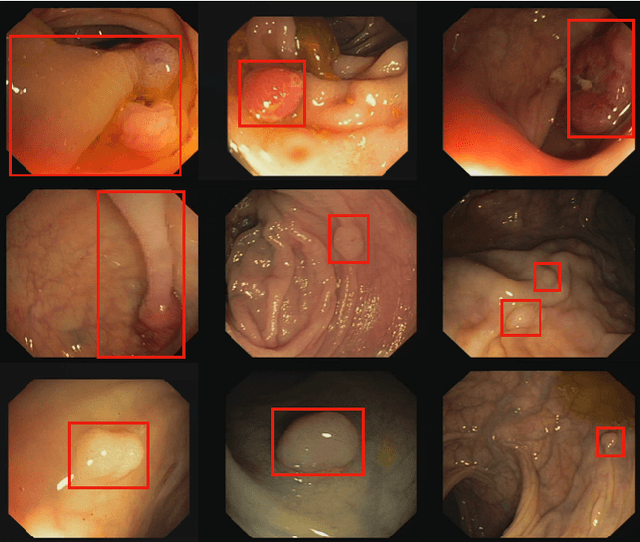

Abstract:Colorectal polyps are abnormal tissues growing on the intima of the colon or rectum with a high risk of developing into colorectal cancer, the third leading cause of cancer death worldwide. Early detection and removal of colon polyps via colonoscopy have proved to be an effective approach to prevent colorectal cancer. Recently, various CNN-based computer-aided systems have been developed to help physicians detect polyps. However, these systems do not perform well in real-world colonoscopy operations due to the significant difference between images in a real colonoscopy and those in the public datasets. Unlike the well-chosen clear images with obvious polyps in the public datasets, images from a colonoscopy are often blurry and contain various artifacts such as fluid, debris, bubbles, reflection, specularity, contrast, saturation, and medical instruments, with a wide variety of polyps of different sizes, shapes, and textures. All these factors pose a significant challenge to effective polyp detection in a colonoscopy. To this end, we collect a private dataset that contains 7,313 images from 224 complete colonoscopy procedures. This dataset represents realistic operation scenarios and thus can be used to better train the models and evaluate a system's performance in practice. We propose an integrated system architecture to address the unique challenges for polyp detection. Extensive experiments results show that our system can effectively detect polyps in a colonoscopy with excellent performance in real time.

Abstract:Colorectal cancer (CRC) is one of the most commonly diagnosed cancers and a leading cause of cancer deaths in the United States. Colorectal polyps that grow on the intima of the colon or rectum is an important precursor for CRC. Currently, the most common way for colorectal polyp detection and precancerous pathology is the colonoscopy. Therefore, accurate colorectal polyp segmentation during the colonoscopy procedure has great clinical significance in CRC early detection and prevention. In this paper, we propose a novel end-to-end deep learning framework for the colorectal polyp segmentation. The model we design consists of an encoder to extract multi-scale semantic features and a decoder to expand the feature maps to a polyp segmentation map. We improve the feature representation ability of the encoder by introducing the dilated convolution to learn high-level semantic features without resolution reduction. We further design a simplified decoder which combines multi-scale semantic features with fewer parameters than the traditional architecture. Furthermore, we apply three post processing techniques on the output segmentation map to improve colorectal polyp detection performance. Our method achieves state-of-the-art results on CVC-ClinicDB and ETIS-Larib Polyp DB.

Abstract:Colorectal cancer (CRC) is a common and lethal disease. Globally, CRC is the third most commonly diagnosed cancer in males and the second in females. For colorectal cancer, the best screening test available is the colonoscopy. During a colonoscopic procedure, a tiny camera at the tip of the endoscope generates a video of the internal mucosa of the colon. The video data are displayed on a monitor for the physician to examine the lining of the entire colon and check for colorectal polyps. Detection and removal of colorectal polyps are associated with a reduction in mortality from colorectal cancer. However, the miss rate of polyp detection during colonoscopy procedure is often high even for very experienced physicians. The reason lies in the high variation of polyp in terms of shape, size, textural, color and illumination. Though challenging, with the great advances in object detection techniques, automated polyp detection still demonstrates a great potential in reducing the false negative rate while maintaining a high precision. In this paper, we propose a novel anchor free polyp detector that can localize polyps without using predefined anchor boxes. To further strengthen the model, we leverage a Context Enhancement Module and Cosine Ground truth Projection. Our approach can respond in real time while achieving state-of-the-art performance with 99.36% precision and 96.44% recall.